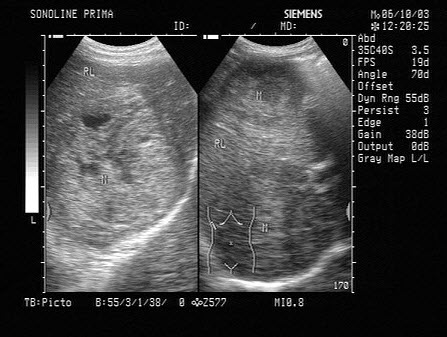

男,57岁,慢性乙肝多年,现上腹痛,纳差,AFP>500,结合超声声像图,诊断为()

[单选题]男,57岁,慢性乙肝多年,现上腹痛,纳差,AFP>500,结合超声声像图,诊断为()A.肝血管瘤B.肝脓肿C.结节性肝硬化D.弥漫性肝癌E.脂肪肝

[单选题]男,57岁,慢性乙肝多年,现上腹痛,食欲缺乏,AFP>500,结合超声声像图,诊断为( )。A.肝血管瘤B.肝脓肿C.结节性肝硬化D.弥漫性肝癌E.

[单选题]男,57岁,慢性乙肝多年,现上腹痛,食欲缺乏,AFP>500,结合超声声像图,诊断为( )。A.肝血管瘤B.肝脓肿C.结节性肝硬化D.弥漫性肝癌E.